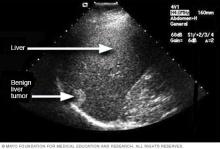

Ultrasound image of a liver tumor

Ultrasound of liver tumor

An ultrasound uses sound waves to create an image. This ultrasound shows a noncancerous liver tumor.